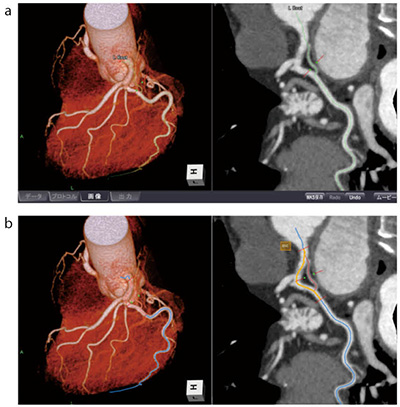

冠動脈についても自動認識された状態で保存され、画像処理時間は大幅に短縮された。しかしながら、冠動脈の曲面多断面再構成(curved multi planar reformat:CPR/cMPR)画像の提供の際には、しっかりと中心を通っていることを確認する必要がある。なぜならば、中心を通っていないと偽狭窄ともとれるCPRとなってしまうからである。ziostation2では中心を確認して、修正が必要な場合には、任意でcross sectionやStretched-CPR、CPRなどを用いて修正することが可能である。また、修正したい部位をクリックすると他の候補ルートが存在する場合、ワークステーションが候補ルートを提示してくれる(図2)。候補ルートに変更したい場合には、候補ルートをクリックするだけで変更することができる。これらの機能は、心臓CT検査における画像処理の負担を大幅に低下させ、従来に比べて画像処理が格段に効率的にできるようになった。

図2 CPR作成画面

a:初期状態 b:他の候補ルートを黄色で表示

CPRを作成する際、血管を正しく認識していない場合には、

修正個所をクリックすることで他の候補ルートが表示される。